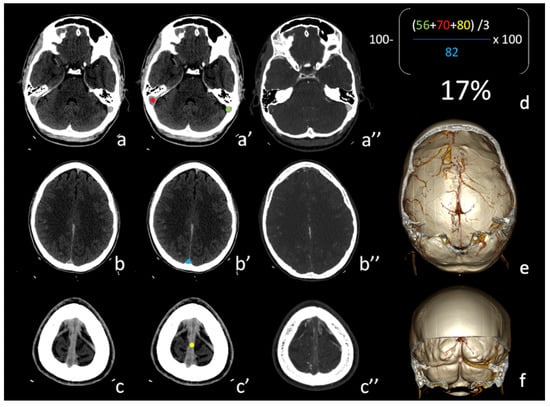

2.5. Image Analysis

3.2. Data Analysis